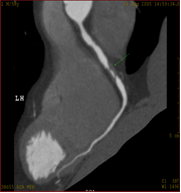

This latest 64 slice CT machine has a special role in Cardiac Angiography, since this investigation has been found to be a viable alternative to catheter angiography. Cardiac coronary Angiography has been found to be highly sensitive and specific in diagnosing coronary artery stenosis, stenosis in coronary stents and occluded coronary bypass grafts. The added advantage of Cardiac CT angiography is that it is completely non invasive, unlike catheter angiography. Also it is the modality to detect and characterize silent non-obstructive atherosclerotic plaques, which may be associated with adverse outcome and cannot be picked up on catheter angiography

Chronic LAD occlusion